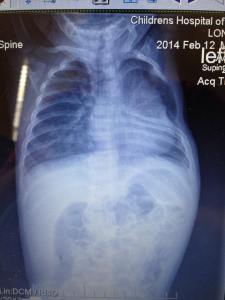

At 20 weeks gestation, we learned that I had a single umbilical artery and also that Ethan’s left kidney measured a little larger than normal. We met with a perinatologist and a genetic counselor and both thought all was well with Ethan despite the new findings. Around 26 weeks, I started having contractions and was put on bed rest. The medications and shots didn’t stop the contractions, so I had two rounds of steroid shots to help develop his lungs in case he came early. I think that because I was being monitored so closely since the contractions started, that’s the only reason they found “issues” with his spine, which was around 28 weeks. At this time, they told me that the kidney resolved and was now normal in size and the ultrasound tech talked with the perinatologist about the spine and he wasn’t concerned. Two weeks later when they saw it again, they ordered a fetal MRI, which showed nothing. Around 33 weeks I saw the perinatologist to discuss MRI results and he took a really good look at the spine and said that he suspected hemivertebrae and missing ribs, but we would just have to wait it out until Ethan was born, but assured me that this wasn’t something to be concerned about….I was very concerned.At 39 weeks 4 days, Ethan was born. He didn’t require anything special, no oxygen, we went to a normal room, he was doing wonderfully, just breathing faster than normal. They didn’t run any tests until a few days later, but we learned that he was missing his left 4th rib, had 4 abnormal ribs above and below the missing rib, had congenital scoliosis and his left kidney was still dilated. At discharge, they set us up with orthopedics and a geneticist, which we saw soon after we were discharged. The geneticist told us that he didn’t feel it was a syndrome, but more so from the two vessel cord and not enough blood flow to the area during development. Orthopedics evaluated him, took an x-ray and said all was well and to come back in a year. This is where something in my gut told me something wasn’t right…a whole year? We saw pulmonology when Ethan was 3 months old and he just said that Ethan may need a surgery when older for his pectus excavatum (sunken chest) but it would be cosmetic.

We went to Philadelphia for the first time in August of 2014, Ethan was 6 months old. We met with an orthopedic surgeon, a thoracic surgeon, a pulmonologist, nutritionist, physical therapy and had x-rays, MRI’s and a CT scan. This is when we found out that Ethan has a partial fusion at T2-3 and T4-5 and a butterfly hemivertebrae at T2. We also learned that his left lung was only able to inflate to 60ml’s, where the right lung was 211ml’s. And, that his left shoulder blade had dropped into his chest cavity where the missing rib is and was attached to his lung, preventing it from expanding. Because of this, our surgeon wanted to do the surgery ASAP, as he thought it would benefit Ethan since it was already greatly involving lung function. The surgeon said that if it weren’t for the shoulder blade being in the chest cavity, we would have waited it out. We had to get weight on Ethan for the surgery, because he breathed so fast, he burned calories much faster than he should have. Surgery was scheduled for 3 months later.